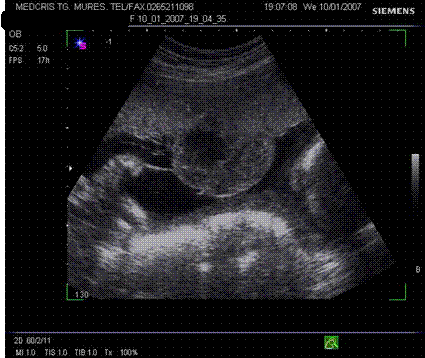

Fig. nr.205. Placenta fundica si posterioara ( normal inserata, cu sageata ) la o sarcina de 16 sapt.

Fig. nr.210. Placenta gr. II la o sarcina de 30 sapt. gestationale, sageata indica proeminenta ondulatiilor dinspre placa choriala , spre placa bazala